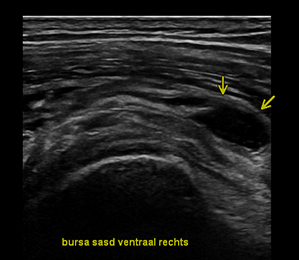

Orthopedische echografie, een blessure nader bekeken .........